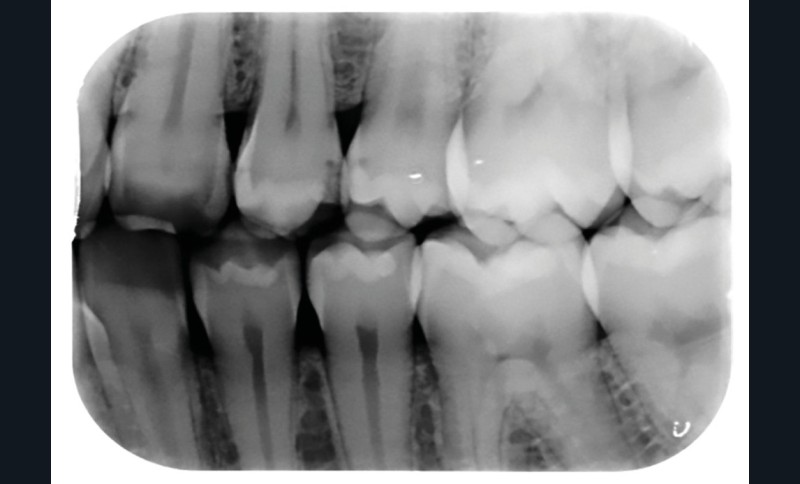

FAUX. Le diagnostic précoce des lésions carieuses se base sur un diagnostic clinique visuel précis à l’aide des classifications visuelles internationales (ICDAS ou ICCMS) et de l’utilisation d’aides optiques (loupes, microscope, caméra avec signal fluorescent ou non) et sur un diagnostic radiographique (à l’aide de deux bitewing, l’un à droite l’autre à gauche) (fig. 1).